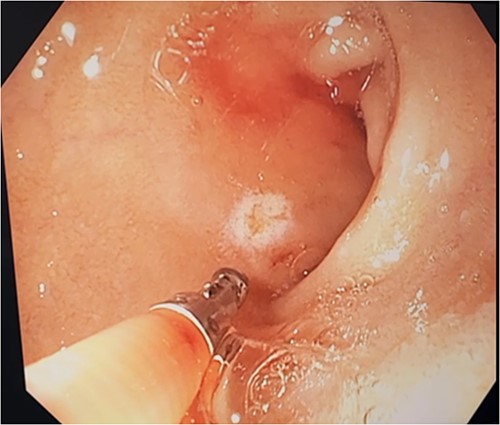

Three days after initial gastroscopy she developed further melena and anaemia, requiring additional PRBCs. She underwent a second gastroscopy, which demonstrated a lesion consistent with a DL at the junction of D1/D2 which was actively bleeding from an exposed vessel (Fig. 3). Haemostasis was achieved with thermocoagulation and adrenaline injection (Fig. 4). The melena resolved and haemoglobin remained stable. The remainder of her admission and 2-month follow-up were unremarkable.

Second gastroscopy – active arterial bleeding at D1/D2 from small mucosal defect without surrounding ulceration.